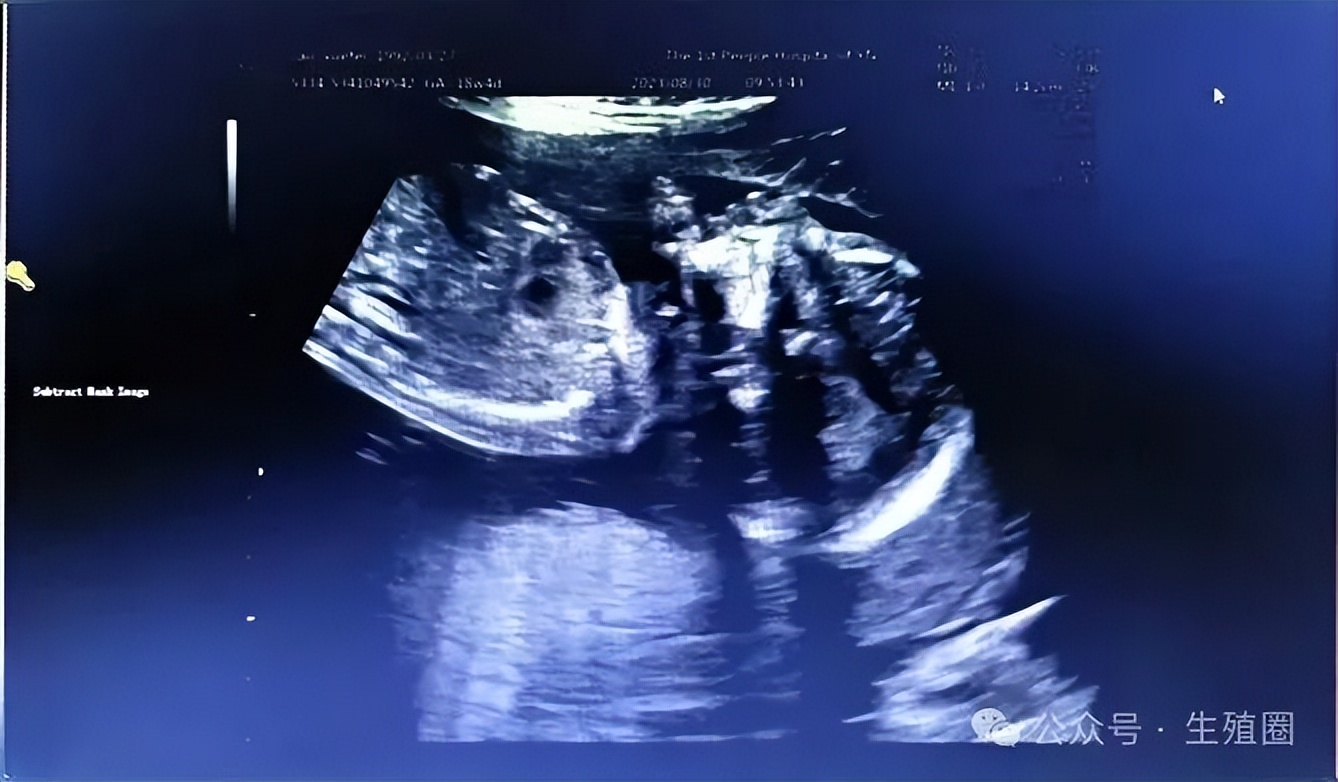

2023年5月11日,患者移植一枚4bb级囊胚,移植14天血清hcg水平为1065mIU/ml。

移植后30天,超声可见胎心后,停用戊酸雌二醇及黄体酮注射液,孕10周时停用黄体酮阴道缓释凝胶,地屈孕酮片减量至每周一次,直至孕12周。

2024年2月1日,患者于孕40周自然分娩一个健康男婴。